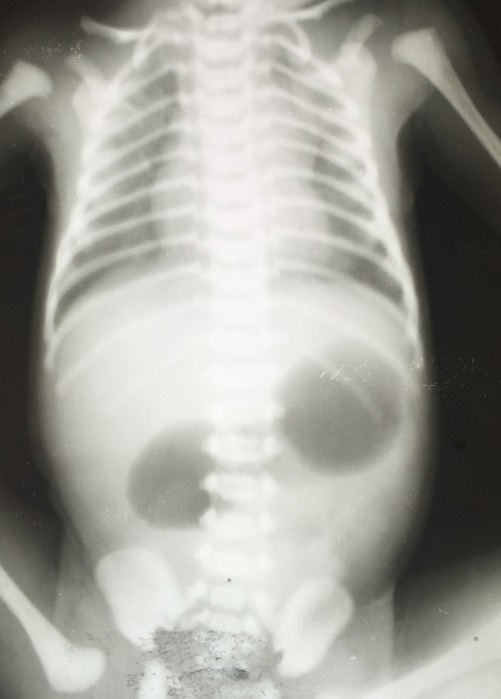

Pada atresia duodenal, foto polos abdomen menunjukkan gambaran khas double-bubble sign, yakni dua buah kumpulan gas atau air-fluid level di abdomen bagian atas yang berasal dari lambung dan bulbus duodenum proksimal yang berdilatasi, sedangkan tidak tampak udara di saluran cerna bagian distal.[1,5]

Pada atresia jejunoileal dan kolon, foto polos abdomen menunjukkan dilatasi loop usus proksimal dari lesi dengan air-fluid level. Semakin distal letak lesi, semakin banyak dilatasi loop usus yang terlihat. Double-bubble sign pada foto polos abdomen dapat dilihat pada Gambar 2.[1,3]

Gambar 2. Double-Bubble Sign pada Atresia Duodenal. Sumber: Openi, 2016